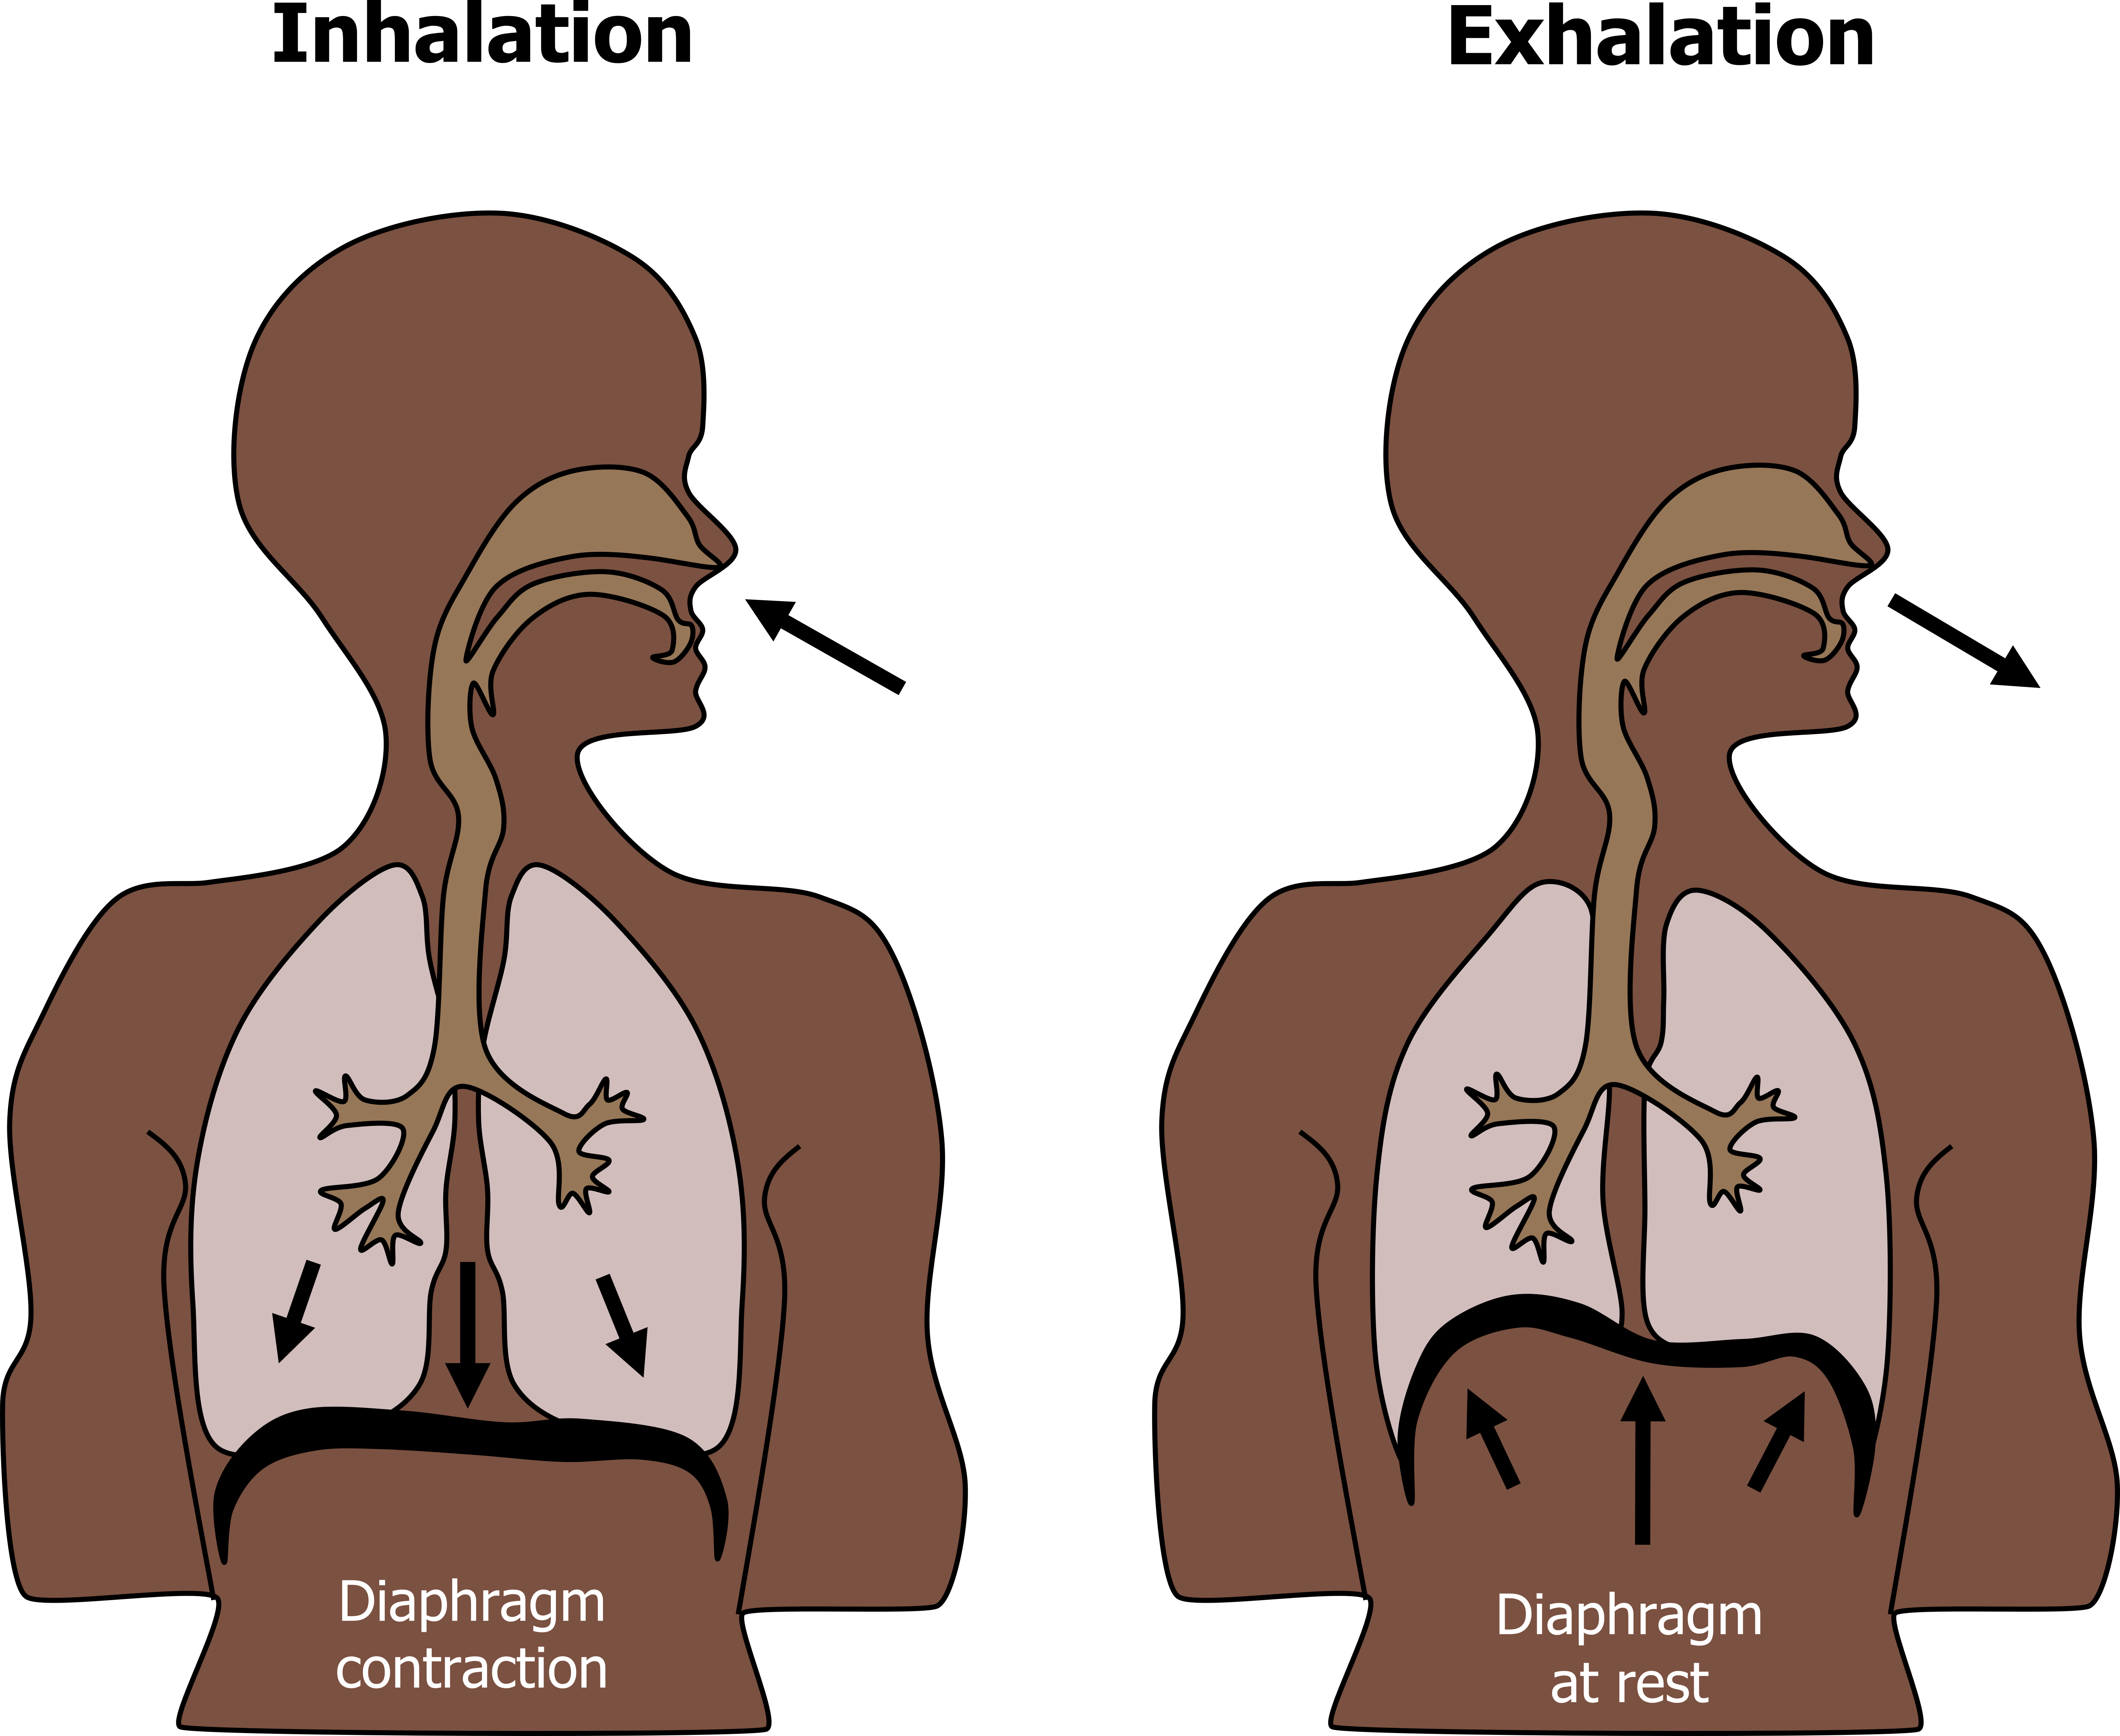

Inspiration And Expiration Chest Size The intercostal muscles contract and move the ribs upwards and outwards This increases the size of the chest and decreases the air pressure inside it which sucks air into the lungs

The diaphragm and external intercostals mediate inspiration and expiration by contracting or relaxing During inspiration the external intercostals and the diaphragm contract expanding the chest wall From a physiological standpoint the lung volumes are either dynamic or static Both subclasses are measured at different degrees of inspiration or expiration however dynamic lung volumes

The intercostal muscles contract and move the ribs upwards and outwards This increases the size of the chest and decreases the air pressure inside it which sucks air into the lungs

Diaphragm Contraction

Inspiration And Expiration Chest Size - The diaphragm and external intercostals mediate inspiration and expiration by contracting or relaxing During inspiration the external intercostals and the diaphragm contract expanding the chest wall